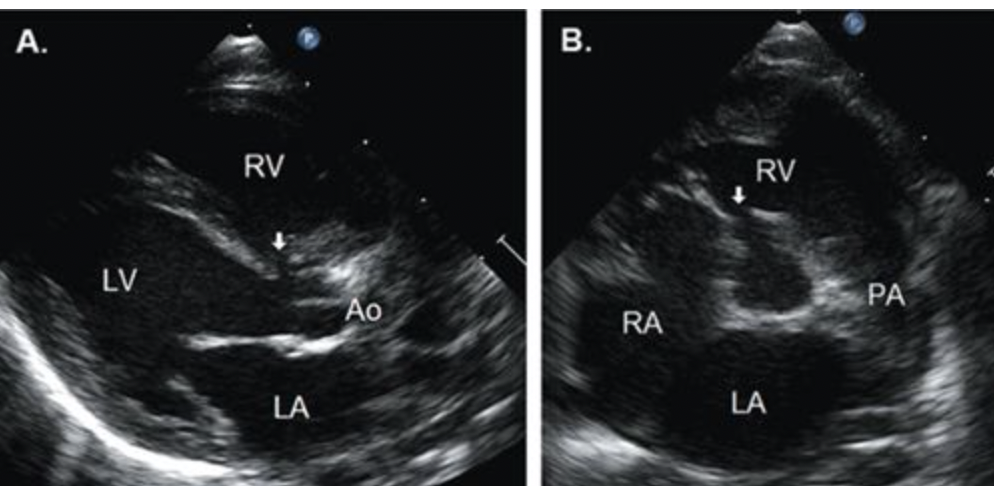

19

Q

What kind of VSD is this?

A

Perimembranous

20

What is this? Be specific

Perimembranous VSD

21

What is this?

22

What specific kind of VSD is this?

Gerbode Defect